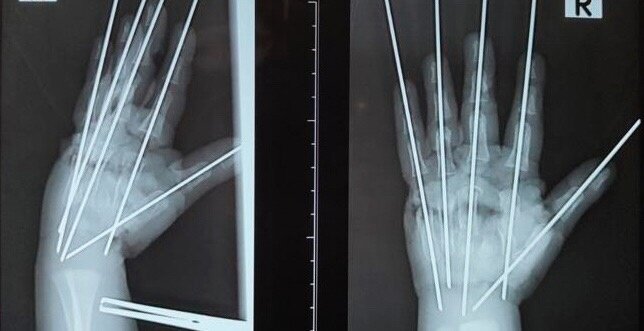

"Повреждена была вся кисть, раздроблены кости, сухожилия, сосуды, нервы. Фактически имела место ампутация – кисть держалась на нескольких связках. Нашей задачей было сохранить жизнеспособные ткани, восстановить анатомию конечности и кровообращение", – рассказал врач.

Хирурги колдовали над поврежденной конечностью более пяти часов. Был выполнен металлоостеозинтез, чтобы соединить раздробленные кости. После потребовалась аутовенозная пластика. Размозженный участок локтевой артерии был заменен фрагментом подкожной вены. После этого пальчики начали розоветь.